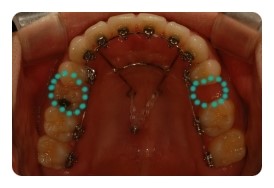

( 상악비교 )

▲ 8월 - 3개월차

▲ 10월 - 5개월차

조신하지못한 저의 잦은 어금니 브라켓탈락 ㅠㅠ 에도 불구하고 잘 이동하고 잇는듯해요